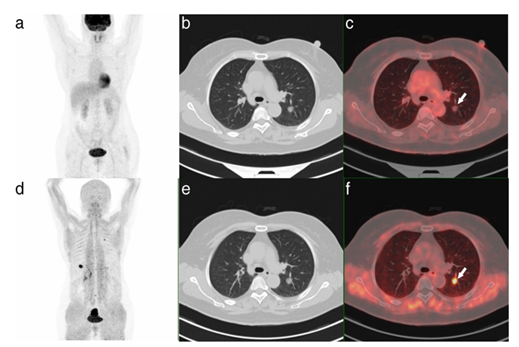

在腫瘤攝取方面,部分患者在2-[18F]FDG顯像中病灶呈陰性,但具有更高的Al18F-NOTA-FAP探針攝取。此外,Al18F-NOTA-FAPI PET/CT在部分患者中較2-[18F]FDG顯示出了更多的轉(zhuǎn)移灶(圖3)。

圖3:[18F]FDG和Al18F-FAPI在女性肺癌患者的PET/CT